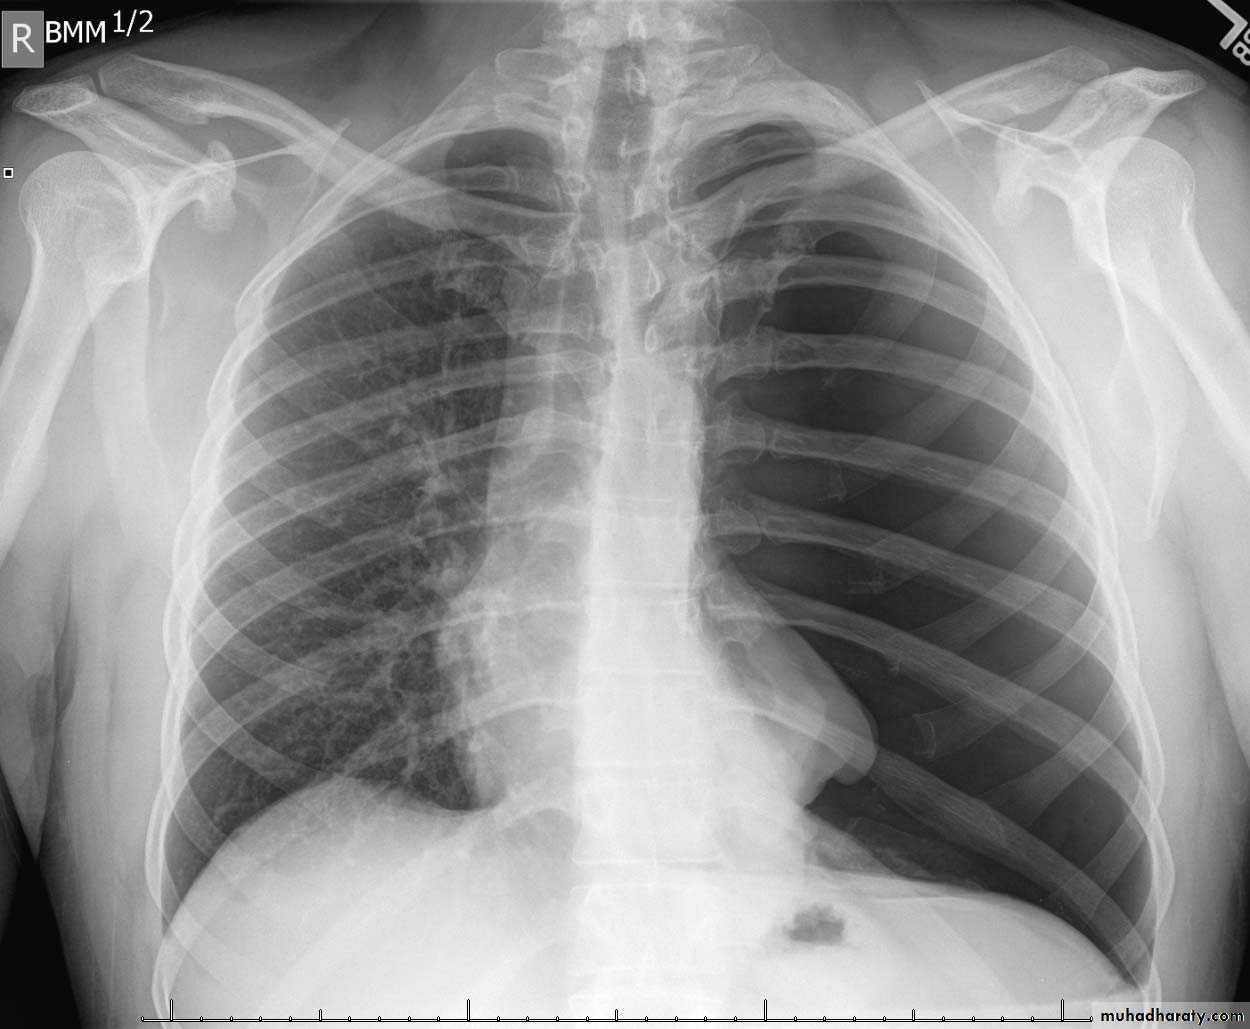

Q ???? Be careful in description & DxBoth of them have similar appearance of broncho pneumonic shadow

??????What is being the pit fall in such films ???

Who can you differentiate ???

62.Q??? Film

63.Q assessment

64.answer this film of Broncho pneumonic (lobular pneumonia ) VS upper zone apical Broncho pneumonic shadow due to post primary TB